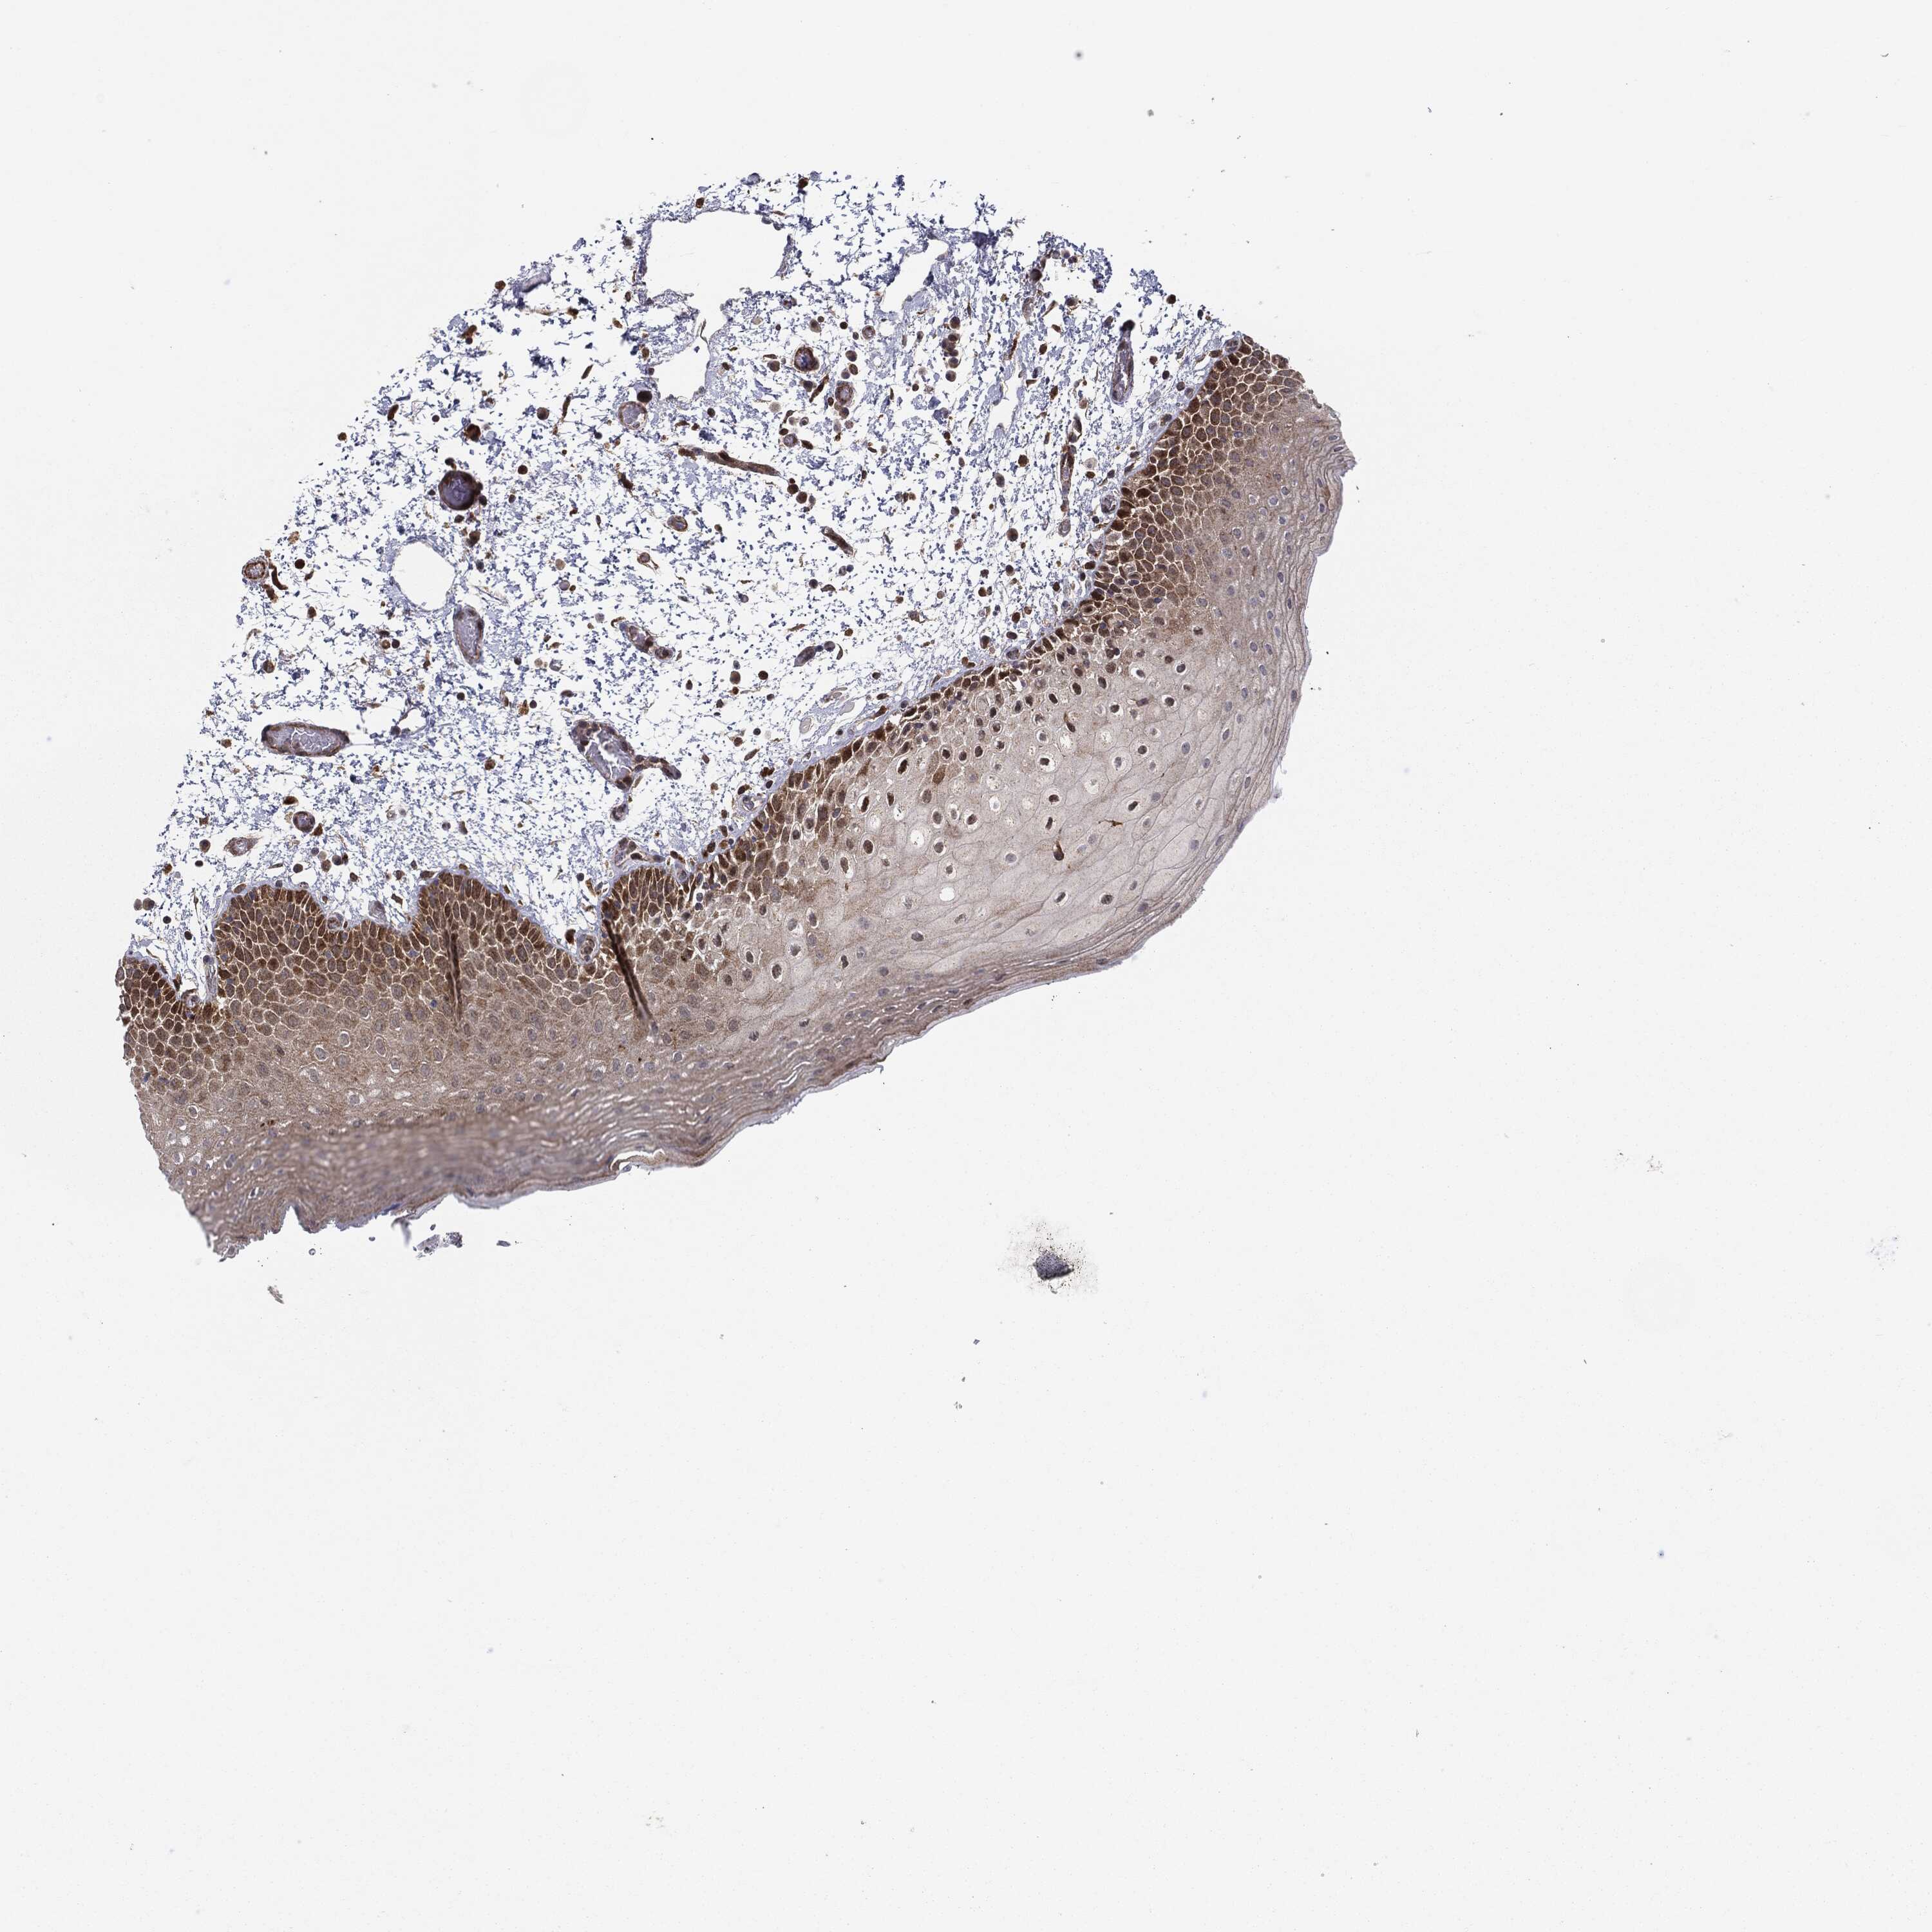

ORAL MUCOSA - Antibody stainingi

Antibody staining in the annotated cell types in the current human tissue is reported as not detected, low, medium, or high, based on conventional immunohistochemistry profiling in selected tissues. This score is based on the combination of the staining intensity and fraction of stained cells.

Each image is clickable and will lead to virtual microscopy that enables deeper exploration of all samples and also displays staining intensity scores, fraction scores and subcellular localization as well as patient and tissue information for each sample.

Antibody HPA031335Antibody CAB004076Antibody CAB080153Antibody CAB080157

Squamous epithelial cells MediumNot detectedNot detectedMedium